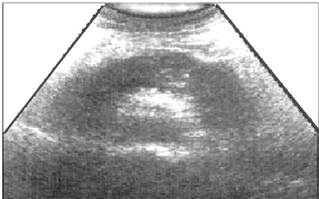

При диффузном поражении неравномерность снижения эхогенности ткани железы связана с неравномерностью выраженности отека в разных ее участках (рис. 9 и 10).

Рис. 9. Эхографическая картина одного из вариантов острого панкреатита (диффузное поражение) в фазе отека железы.

Рис. 10. Эхографическая картина одного из вариантов острого панкреатита (диффузное поражение) в фазе отека железы с распространением отека на околопанкреатическую клетчатку. Контуры железы неотчетливые, “размытые”.